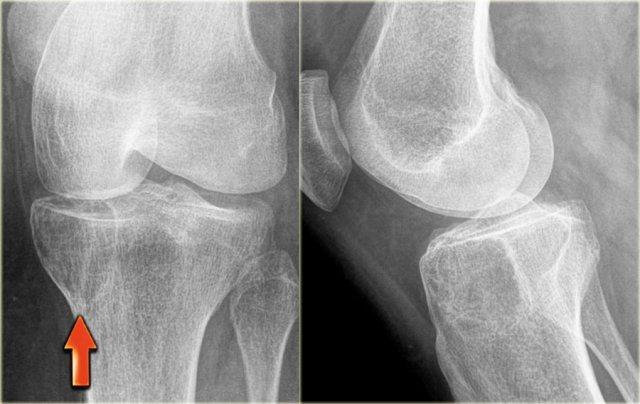

Hình ảnh bên trái của một u xơ sụn dạng nhầy (CMF).

Có một tổn thương tiêu xương lệch tâm ở vùng hành xương của đầu gần xương chày.

Ở phía trong có một bờ xơ cứng.

Ở phía ngoài có sự phá hủy vỏ xương đều đặn với lớp xương ngoại vi.

Hình ảnh MRI cũng cho thấy bờ xơ cứng với cường độ tín hiệu thấp.